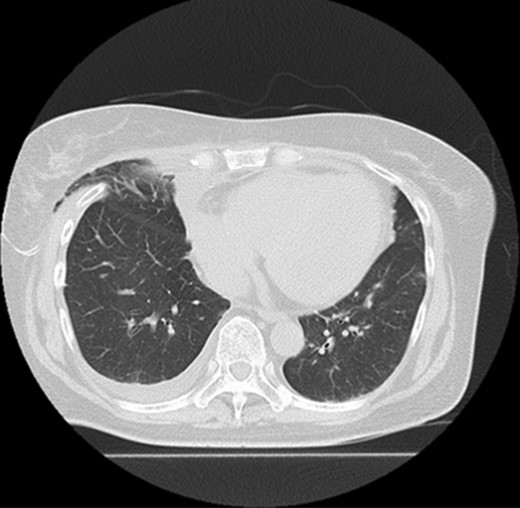

Five days after surgery, she complained of right chest wall pain and discomfort on inspiration. Computed tomography (CT) revealed that part of the right upper lobe of the lung had herniated through the right fourth intercostal space (Fig. 1). Lung hernia was diagnosed. The herniated lung was manually repositioned by compression bandages (Fig. 2). On postoperative Day 11, 6 days after recognition of the herniation, the lung hernia was not apparent on CT. The patient was discharged home without symptoms on postoperative Day 12.

Manual repositioning of the herniated lung by compression bandages.